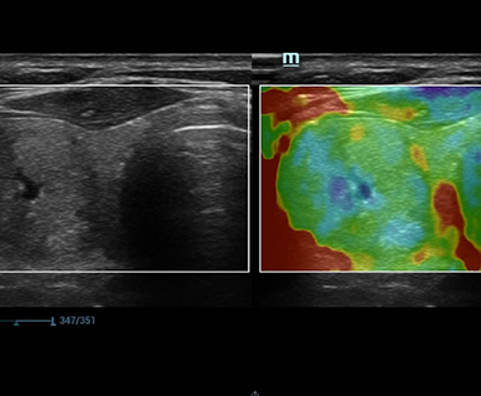

Desde su creaciÃģn, Mindray no ha dejado de explorar nuevas maneras de mejorar la fiabilidad del diagnÃģstico. Gracias a ZONE Sonography?, la tecnologÃa mÃĄs revolucionaria, la nueva plataforma ZST+ del Resona 7 eleva la calidad de imagen de ultrasonido mediante la adquisiciÃģn de zonas y el procesamiento de datos de canal.

AdemÃĄs de una calidad superior de la imagen, el Resona 7 tambiÃĐn mejora las capacidades de investigaciÃģn clÃnica gracias al revolucionario V Flow para la evaluaciÃģn hemodinÃĄmica vascular y la adquisiciÃģn de planos mÃĄs inteligente a partir de un conjunto de datos 3D para el diagnÃģstico CNS fetal. Combinando el funcionamiento multitÃĄctil mÃĄs intuitivo basado en gestos y todas las funciones clÃnicas esenciales, el Resona 7 estÃĄ realmente encabezando nuevas ondas en la innovaciÃģn del campo del ultrasonido.